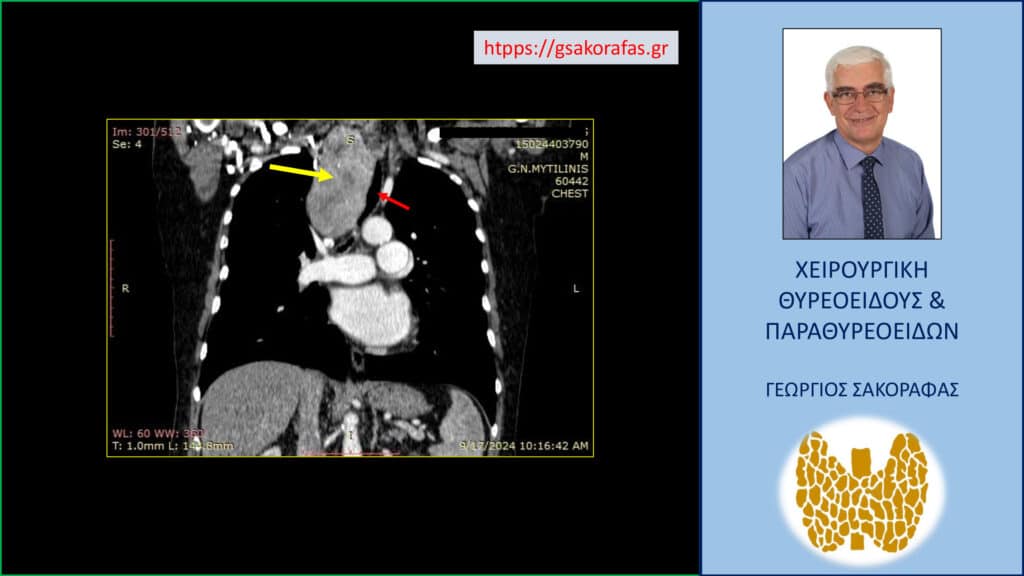

- Γιατί είμαστε σε θέση να εκτελέσουμε με ασφάλεια και αποτελεσματικότητα κάθε είδους χειρουργική επέμβαση θυρεοειδούς – παραθυρεοειδών, ακόμη και σε επιπλεγμένα (δύσκολα) περιστατικά, όπως εκτεταμένοι λεμφαδενικοί καθαρισμοί σε καρκίνο θυρεοειδούς, επεμβάσεις σε λίαν ευμεγέθεις καταδυόμενες στο μεσοθωράκιο βρογχοκήλες, υποτροπές παθήσεων θυρεοειδούς (συμπεριλαμβανομένου του καρκίνου θυρεοειδούς), υποτροπές υπερπαραθυρεοειδισμού, αδενώματα παραθυρεοειδών σε έκτοπη θέση ή λόγω υπεράριθμων παραθυρεοειδών, διάχυτη υπερπλασία παραθυρεοειδών, κλπ.